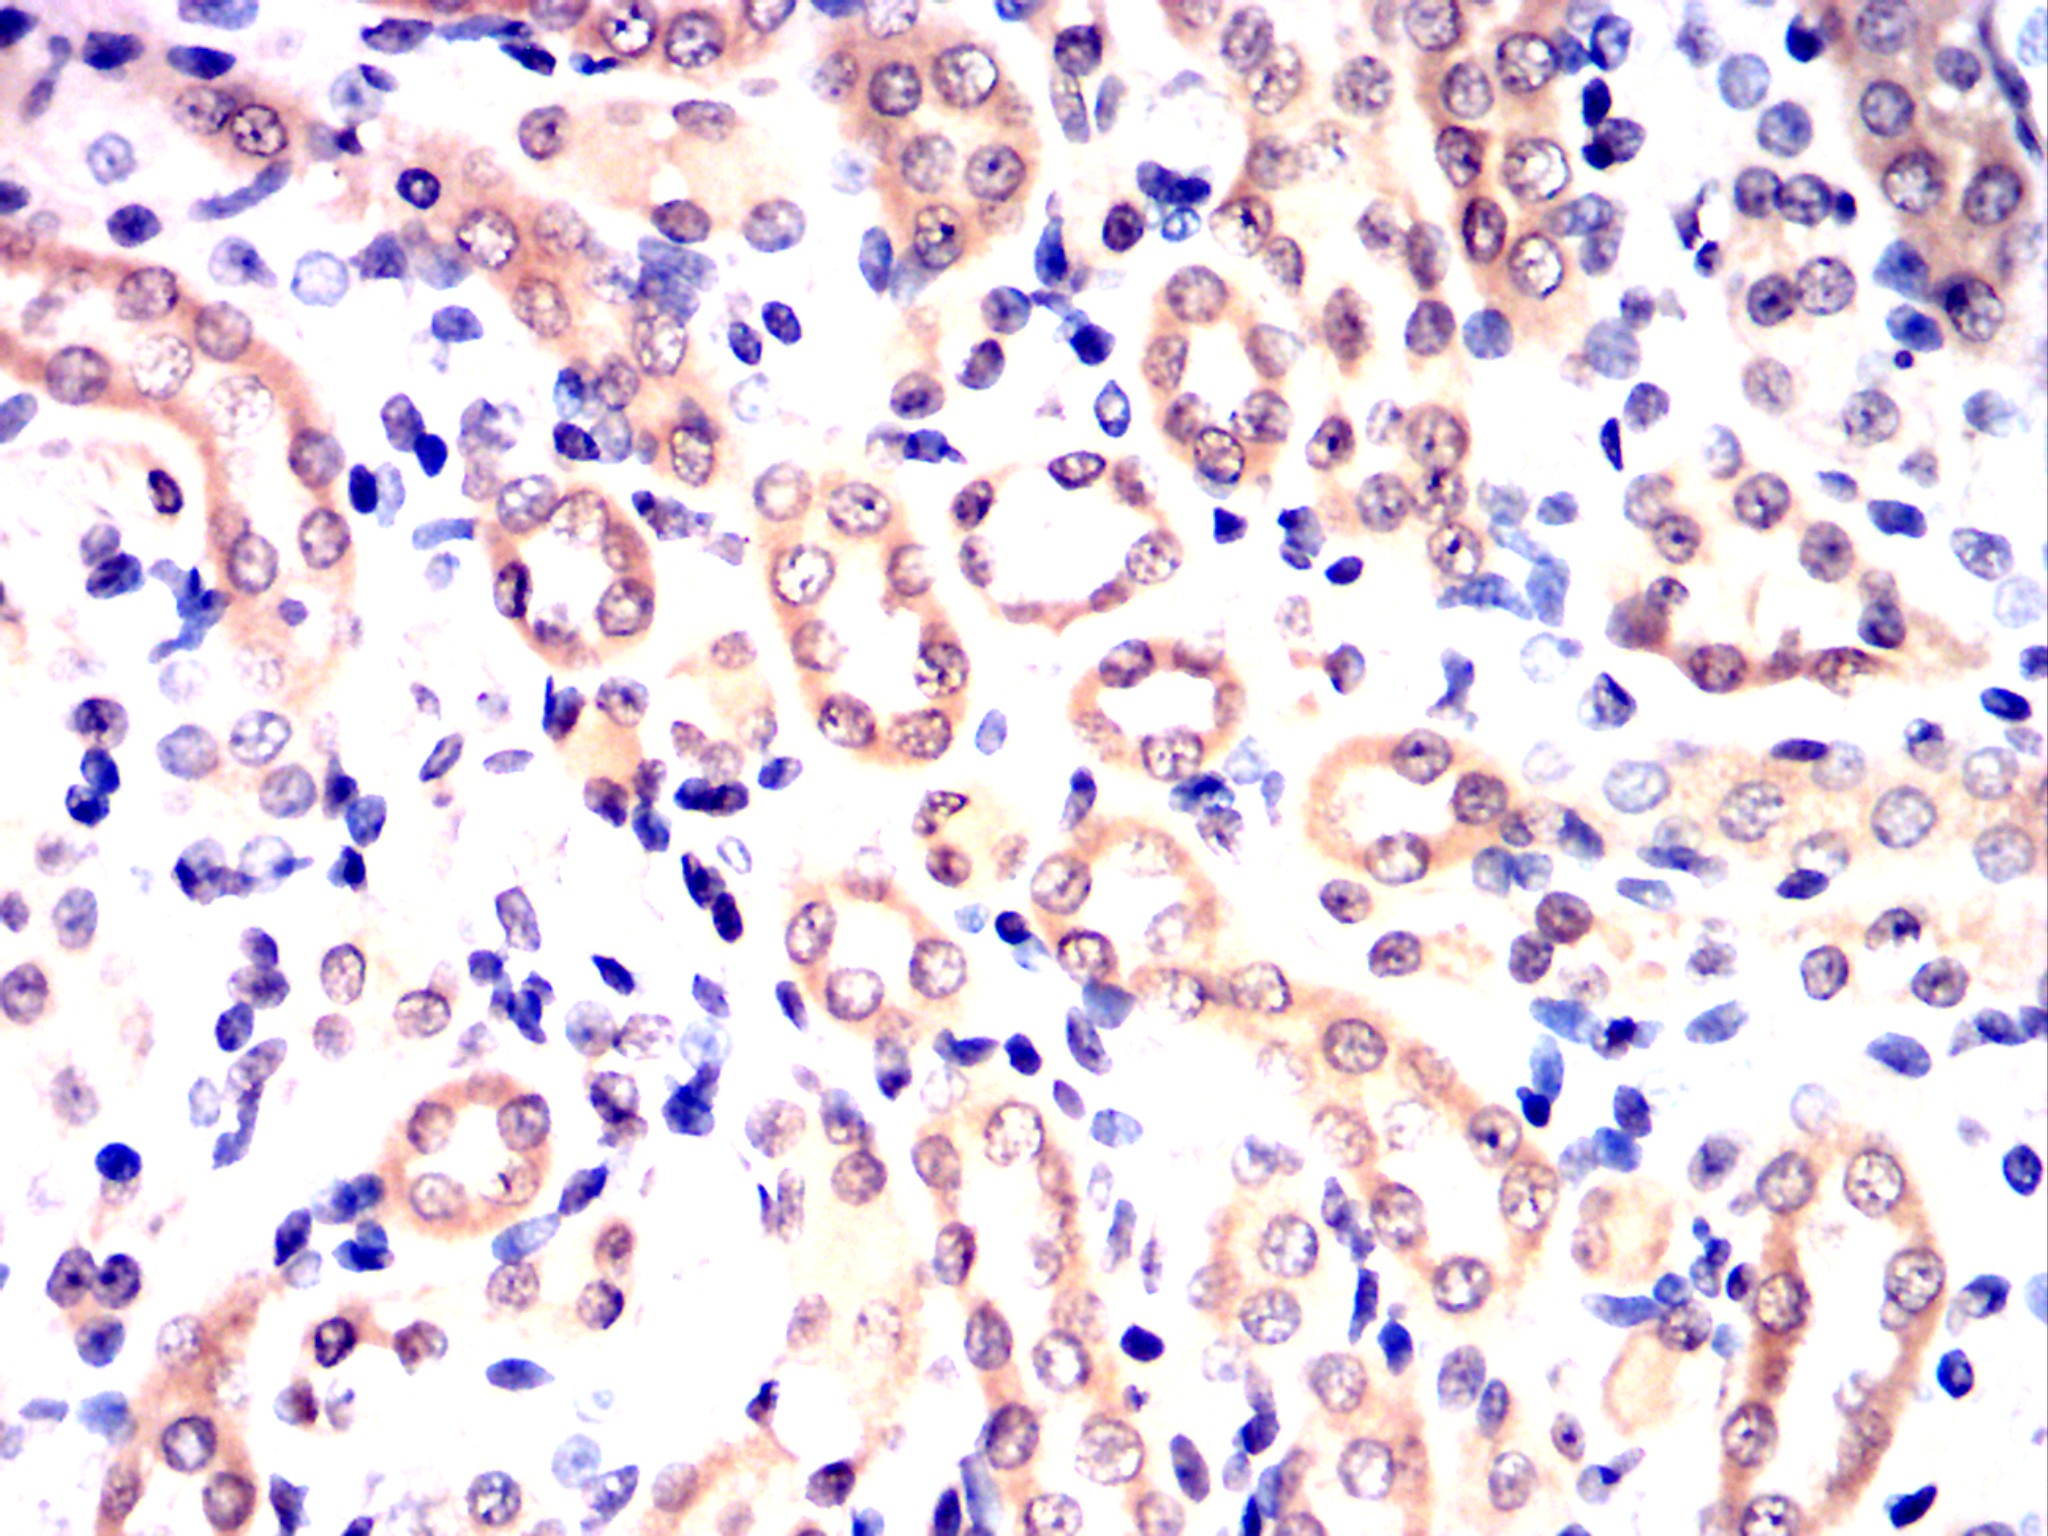

Immunohistochemical analysis of paraffin-embedded human rectum cancer tissues (left) and placenta tissues (right) using CDK9 mouse mAb with DAB staining.